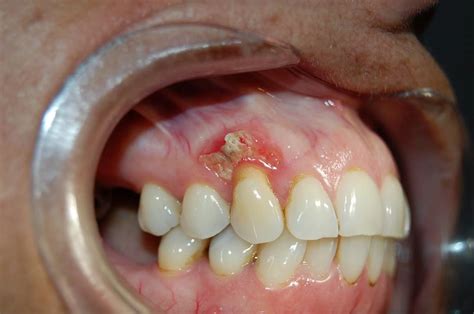

El uso de bifosfonatos está asociado con condiciones patológicas, como es la osteonecrosis de la mandíbula, patología que se produce en un área del hueso que ha perdido el suministro de sangre. Los pacientes con osteonecrosis, también conocida como necrosis avascular de la mandíbula, desarrollan hueso expuesto que no cicatriza, y a menudo es dolorosa.

Esta patología se ha definido como la presencia de hueso expuesto en la región maxilofacial que no cicatriza dentro de las 8 semanas posteriores a la identificación por parte de un profesional de la salud. Esta enfermedad ósea presenta dolor, hinchazón o infección en la mandíbula.

- Presencia de una o varias lesiones ulceradas en la mucosa de los procesos alveolares, con exposición del hueso maxilar o mandibular. También pueden existir casos sin exposición ósea, con dolor o fístulas, que deben ser considerados como candidatos para realizar un estudio más detallado.

- El hueso expuesto presenta un aspecto necrótico.

- Ausencia de cicatrización durante un periodo de, al menos, 6 semanas.